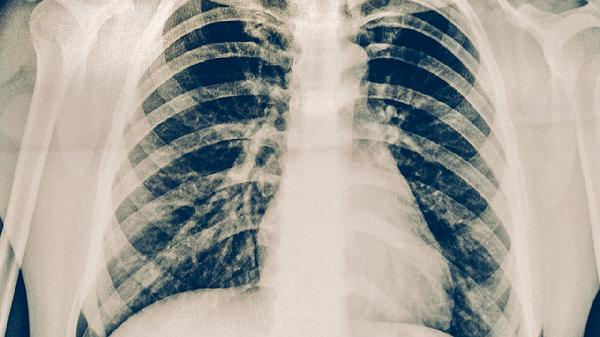

胸部CT通过断层扫描能清晰显示肺部微小病灶,对早期肺癌的检出率明显优于普通胸片。低剂量螺旋CT可发现直径2-3毫米的肺结节,通过分析结节形态、密度、边缘特征等,能初步判断良恶性。对于典型肺癌表现如分叶状肿块、毛刺征、胸膜凹陷等,CT诊断准确率较高。增强CT还能观察肿瘤血供情况,辅助判断纵隔淋巴结转移。

部分特殊类型肺癌在CT上可能表现不典型,如磨玻璃样结节需定期随访观察变化,部分肺泡癌可能仅表现为斑片状阴影。极少数情况下,早期中央型肺癌若病灶被血管或支气管遮挡,可能存在漏诊可能。对于高度怀疑肺癌但CT未明确显示的患者,需结合支气管镜或穿刺活检进一步确诊。